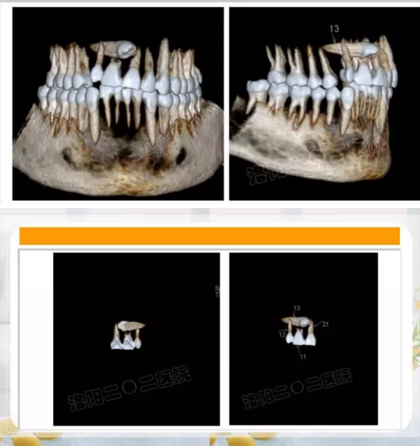

這些逆襲的牙齒真的沒(méi)辦法嗎?。。。

第一種方法:糾正過(guò)來(lái)!

21.png

第二種方法:干掉它!

22.png

第三種方法:不管它唄!

23.png

阻生齒外科聯(lián)合正畸治療